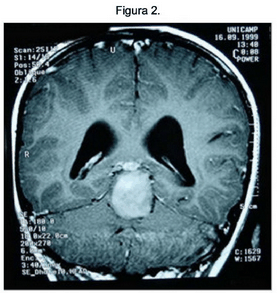

Corte Coronal T1 com contraste. Fonte: UNICAMP. Anatomopatológico.

Disponível em: http://anatpat.unicamp.br'radastropilo2.html.Acessado em 21/09/2013.

Nos cortes pesados em T2 a lesão mostra-se predominantemente homogênea e com hipersinal, indicando tratar-se de uma lesão hidratada. Não há componente cístico. Os cortes sagitais, T1 com contraste mostram Tumor Sólido, bem delimitado, originado na placa quadrigêmea; comprime anteriormente o mesencéfalo e posteriormente a porção anterior do vermis. Impregna-se de forma difusa e levemente heterogênea. O halo de liquor em volta da lesão na cisterna cerebelar superior demonstra que o tumor provém do mesencéfalo. Os cortes coronais T1 em contraste mostram que o tumor é originado na placa quadrigêmea deforma o III ventrículo (Situa-se no nível da incisura do tentório e eleva a pineal, mas não a invade).